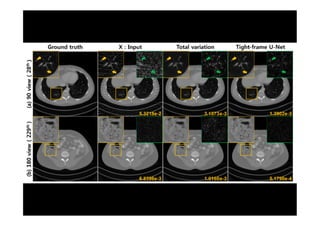

Improving U-net using Deep Conv Framelets

• Dual Frame U-net

• Tight Frame U-net

JC Ye et al, SIAM Journal Imaging Sciences, 2018

Y. Han and J. C. Ye, TMI, 2018

U-Net versus Dual Frame U-Net

Tight-Frame U-Net

Han et al, TMI, 2018

90 view recon

U-Net vs. Tight-Frame U-Net

• JC Ye et al, SIAM Journal

Imaging Sciences, 2018

• Y. Han and J. C. Ye, TMI,

2018

Problem of U-net Poolingdoes NOT satisfy the frame condition JC Ye et al, SIAM Journal Imaging Sciences, 2018 Y. Han et al, TMI, 2018. ext > ext = I + > 6= I

Improving U-net usingDeep Conv Framelets • Dual Frame U-net • Tight Frame U-net JC Ye et al, SIAM Journal Imaging Sciences, 2018 Y. Han and J. C. Ye, TMI, 2018

Tight-Frame U-Net JC Yeet al, SIAM Journal Imaging Sciences, 2018 Han et al, TMI, 2018

90 view recon U-Netvs. Tight-Frame U-Net • JC Ye et al, SIAM Journal Imaging Sciences, 2018 • Y. Han and J. C. Ye, TMI, 2018